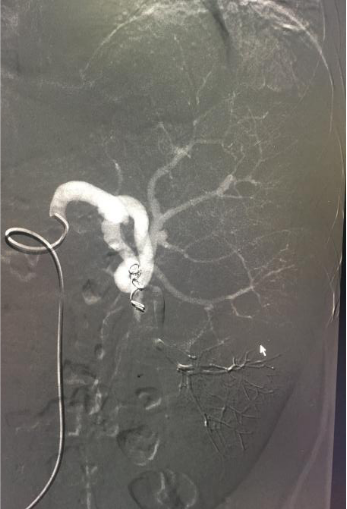

脾功能亢进是肝硬化最常见并发症,脾脏肿大,血细胞过分漪留脾脏内,使其破坏增多,导致白细胞明显下降易致感染,红细胞下降致贫血,血小板明显下降易致出血。 脾脏又是免疫器官。选择性脾动脉栓塞后,部分脾实质缺血性梗死、液化、机化、萎缩、纤维结缔组织增生,使脾脏缩小,削弱脾脏破坏血细胞的能力,使外周血细胞回升,纠正脾亢,同时保留其免疫功能(见图2,栓塞后脾脏造影)。

脾动脉瘤是最常见的内脏动脉瘤之一,其发病率仅次于腹主动脉瘤和髂动脉瘤,居腹部动脉瘤第三位。脾动脉瘤危险性极大,由于症状隐匿,常规体检不易发现,一旦破裂,死亡率高达20%~70%。因此早期诊断极为重要,争取在动脉瘤破裂前及时介入治疗或手术。介入手术是近十年发展起来的新技术,目前已经成为脾动脉瘤首选治疗方式,它主要包括弹簧圈栓塞术、覆膜支架植入、裸支架置入弹簧圈栓塞术等,具有灵活、简便、恢复快等优点。而传统开腹手术创伤大,术后住院时间长,并且容易出现一系列术后并发症,如结扎点出血及胰漏等。

该患者在我院放射科接受经股动脉穿刺入路行脾动脉及脾动脉瘤栓塞术治疗(见图2),术后第二天即可下床活动,大腿根部只有约2毫米的穿刺点。1周后出院复查血常规白细胞数:5.4*109/L(正常值为3.5-9.5*109/L),血小板数55.0*109/L(正常值为100-300*109/L)。经过介入栓塞治疗,不仅解决了脾脏功能亢进的问题,而且小炸弹顺利拆除。此外,还一定程度上缓解了门静脉压力,预防上消化道再出血,可谓是“一箭三雕”之效。